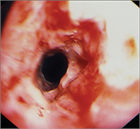

1. 急性期の病状把握のためCT、上部消化管内視鏡検査は必要である(推奨度2)

1. 受傷数日後から2週間程度は内視鏡検査を避けるべきである(推奨度2)